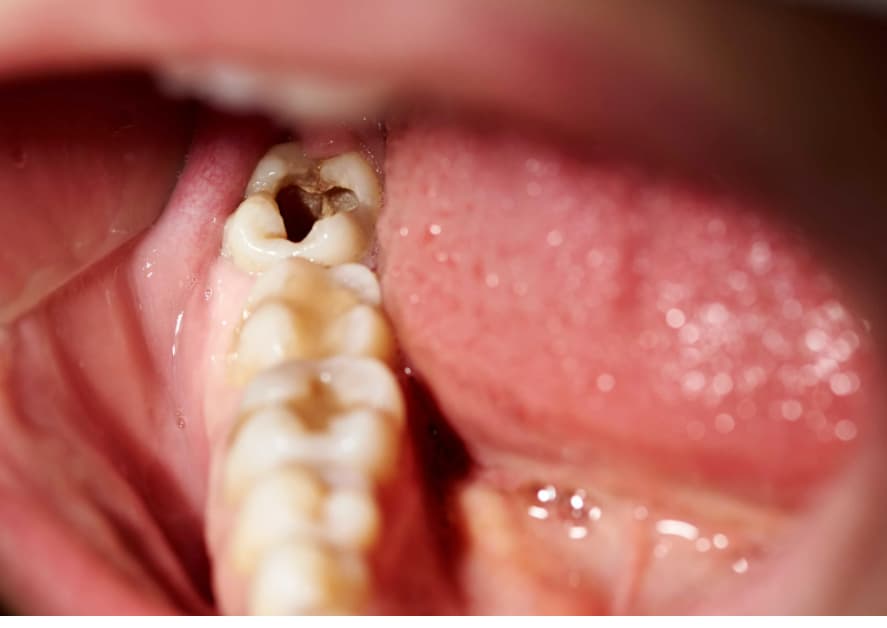

(Sâu răng nặng có trám được không sẽ còn tùy thuộc vào mô răng mất, tình trạng răng, tay nghề của bác sĩ)(**)

(Ca lâm sàng trám răng sâu nặng giúp cải thiện chức năng ăn nhai được điều trị tại Peace Dentistry)(**)